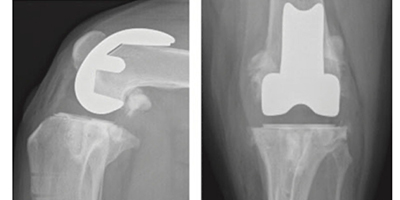

인공 무릎관절 치환술 Total Knee Replacement (TKR) 슬관절

슬관절 인공관절 수술은 중증의 골관절염이나 이전 수술(TPLO, TTA 등) 이후 심한 관절 변형 또는 강직으로 일상적인 보행이 어려운 경우에 시행됩니다.

특히 슬개골 탈구, 십자인대 파열 등으로 반복적인 수술과 관절 손상이 누적된 환자에서 고려됩니다. 과거에는 관절 고정술(stifle arthrodesis)이 대안이었으나, 정상적인 관절 각도 유지와 보행 기능 회복을 위해서는 인공 무릎관절 치환술이 더 나은 선택이 될 수 있습니다.